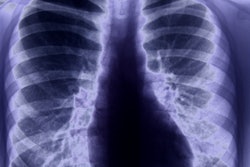

SAN JOSE, CA - Does radiology need a reality check when it comes to artificial intelligence (AI)? In a talk at this week's Nvidia GPU Technology Conference (GTC 2019), Dr. Paul Chang of the University of Chicago raised just that question, proposing that workflow in healthcare must be fixed before AI can reach its full potential.

Dr. Paul Chang from the University of Chicago.